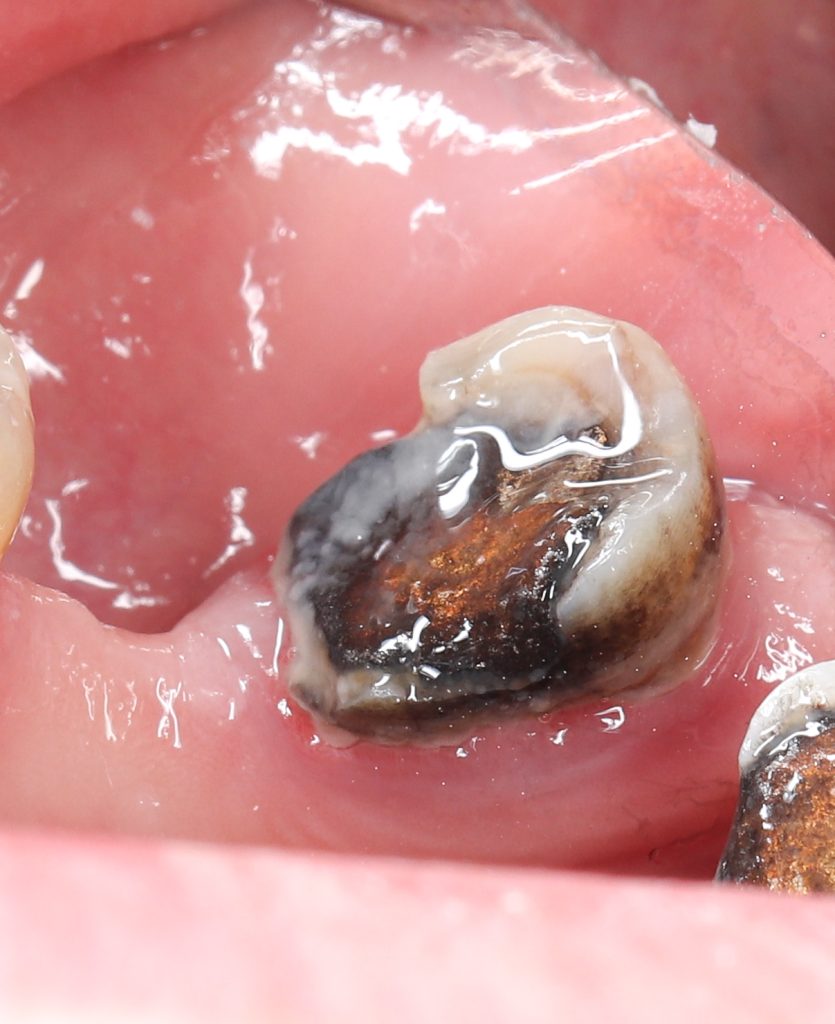

Tooth drifted mesially as 6 was extracted long time ago which made it difficult in isolation & matricing

🔹Old amalgam & caries removal

🔹DME